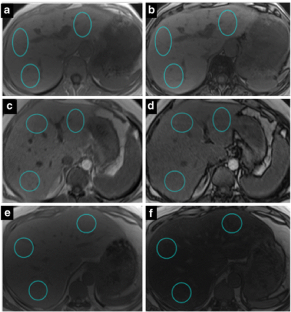

Fig. 4

Fig. 5

Fig. 6